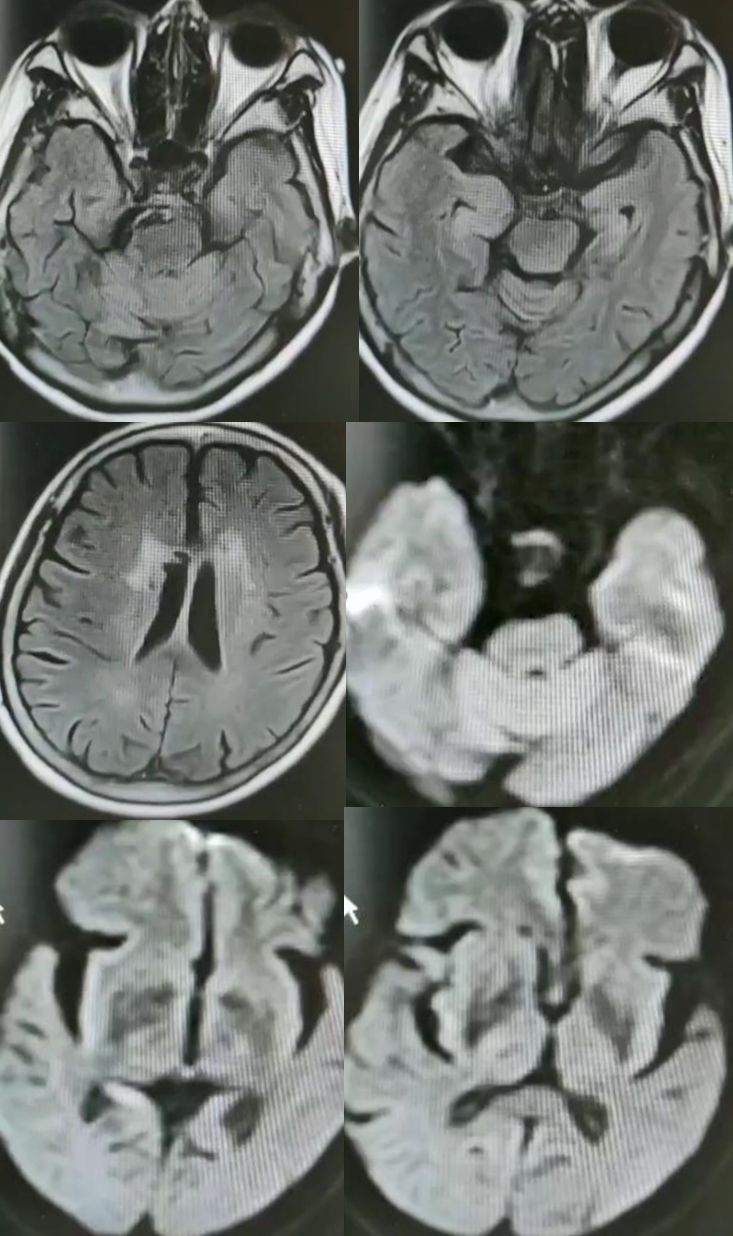

女,36岁,突发意识障碍伴抽搐。

答案:狼疮脑病合并可逆性后部白质脑病综合征(PRES)。补充病史:SLE病史。患者青年女性,有SLE病史,发作性神经系统症状,结合影像学考虑PRES。轻度PRES表现为皮质下或皮质下白质水肿,无实质出血、占位效应、或仅累及脑干或基底节中的一个。中度PRES表现为融合性水肿,从皮质向深部白质延伸,但不延伸至脑室边缘,小脑、脑干或基底节区中有两个轻度受累。重度PRES表现为从皮层到脑室的融合性水肿,或水肿或出血引起中线移位,小脑、脑干或基底节区均受累。

PRES本质上是一种可逆性的血管源性水肿,伴急性神经系统症状,如癫痫发作,脑病,头痛,视觉障碍等。常见原因为:高血压、肾衰竭、使用细胞毒*药性**物、自身免疫性疾病、子痫前期或子痫。约半数PRES患者既往有自身免疫性疾病,如:SLE、血栓性血小板减少性紫癜、甲减、硬皮病、Crohn病、溃疡性结肠炎、类风湿性关节炎、干燥综合征、结节性多动脉炎、肉芽肿性血管炎和视神经血管炎。PRES常由急剧的血压波动或细胞因子对血管壁的直接作用致内皮损伤,引起血脑屏障的破坏,继而引起脑水肿。对称性枕叶皮质下病变要和MELAS鉴别,二者形似神也似。MELAS 的MRI 表现为后部皮层信号改变、脑萎缩、基底节信号改变和钙化、脑白质营养不良。急性期通常会出现 T2 和 FLAIR 高信号,DWI 成像弥散受限。